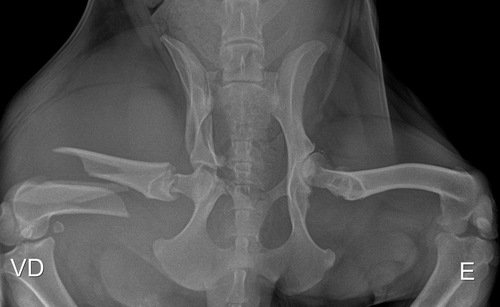

Essa é a Rute, foi atropelada na segunda feira de carnaval, foi resgatada porém não temos o valor para fazer a cirurgia, ela teve múltiplas fraturas e uma bem grave com risco de se tornar exposta!! Precisamos muito da ajuda de todos vocês para que a Rute possa ser operada o mais rápido possível..